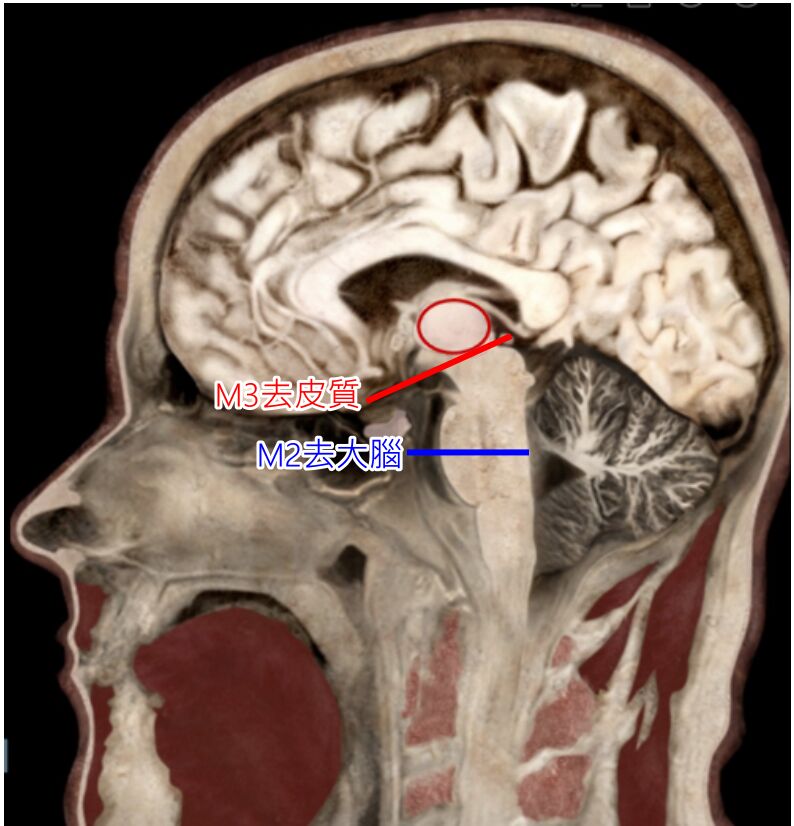

題目圖片傷害點在四疊體上丘之上,是M3去皮質

重新標示一下題目的圖,M2、M3大至是這樣切的

中腦(含)以下是去大腦

間腦(含)以上是去皮質

正確(B) 去皮質僵直:上肢屈曲及下肢伸直反應